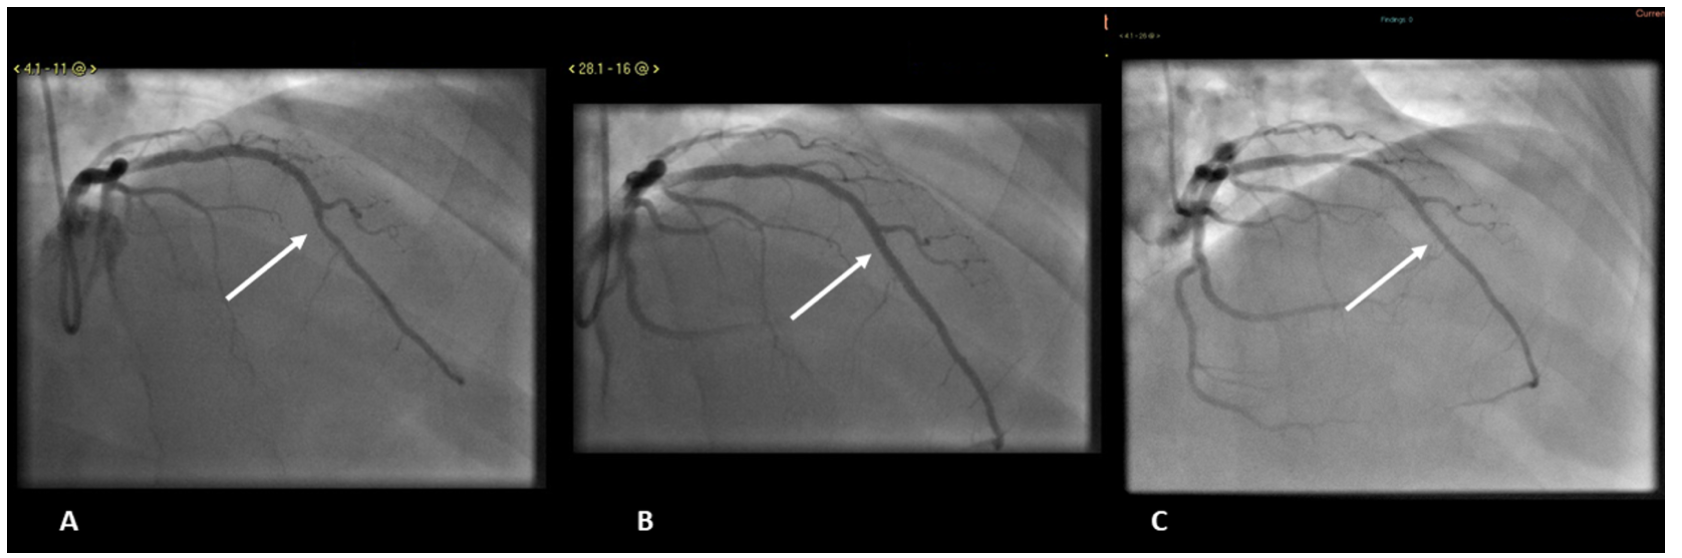

Patient 1. A 51-year-old male patient presented with recurrent angina. His coronary angiogram revealed MB with 70% narrowing in the mid-LAD and otherwise normal epicardial vessels. Physiological functional assessment revealed borderline measurements with a resting full-cycle ratio (RFR) of 0.89 and a fractional flow reserve (FFR) of 0.82. IVUS confirmed the presence of an MB in the mid-LAD with the characteristic radiolucent “half-moon” appearance (Figure 1). Additionally, mild atheroma was present proximal to the tunneled segment (Figure 1). The patient was originally treated medically; however, due to persistent symptoms, the patient was readmitted and underwent PCI. The mid-LAD was implanted with 2 DESs (3.0 x 15 mm and 3.5 x 8 mm) with postdilation, with optimal angiographic results (Figure 1). On this occasion, no FFR study was done and no post stenting was obtained. His symptoms resolved and he remains entirely asymptomatic at 3-year follow-up. He had 1 episode of atypical chest pain 28 months later. Repeat coronary angiography at this time showed patent stents with no in-stent restenosis (Figure 1).